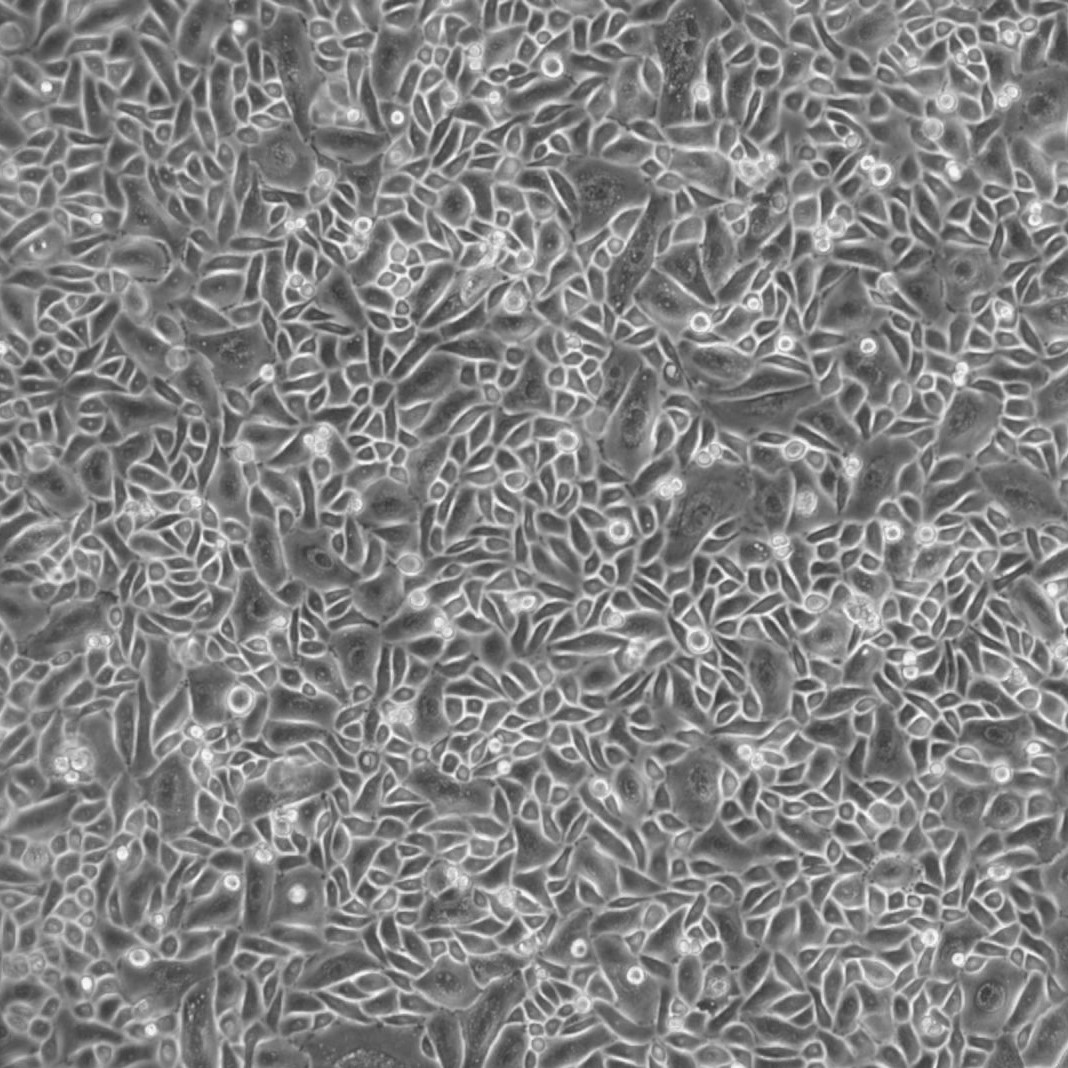

Diseased Human Small Airway Epithelial Primary Cells — Asthma + COPD (Chronic Obstructive Pulmonary Disease).

These primary cells have been isolated from tissue, plated onto culture vessels, expanded, harvested and cryopreserved.

Lifeline® Human Small Airway Epithelial Cells, when grown in BronchiaLife™ medium, provide an ideal serum-free culture model for the accurate studies of asthma, pathogenesis, or pharmacology.

Human Airway Epithelial Cells are cultured without retinoic acid and cryopreserved as primary cells to ensure the highest viability and plating efficiency. Lifeline® Human Small Airway Epithelial Cells are quality tested in BronchiaLife™ Medium to ensure proper growth and morphology over a period of at least 15 population doublings.